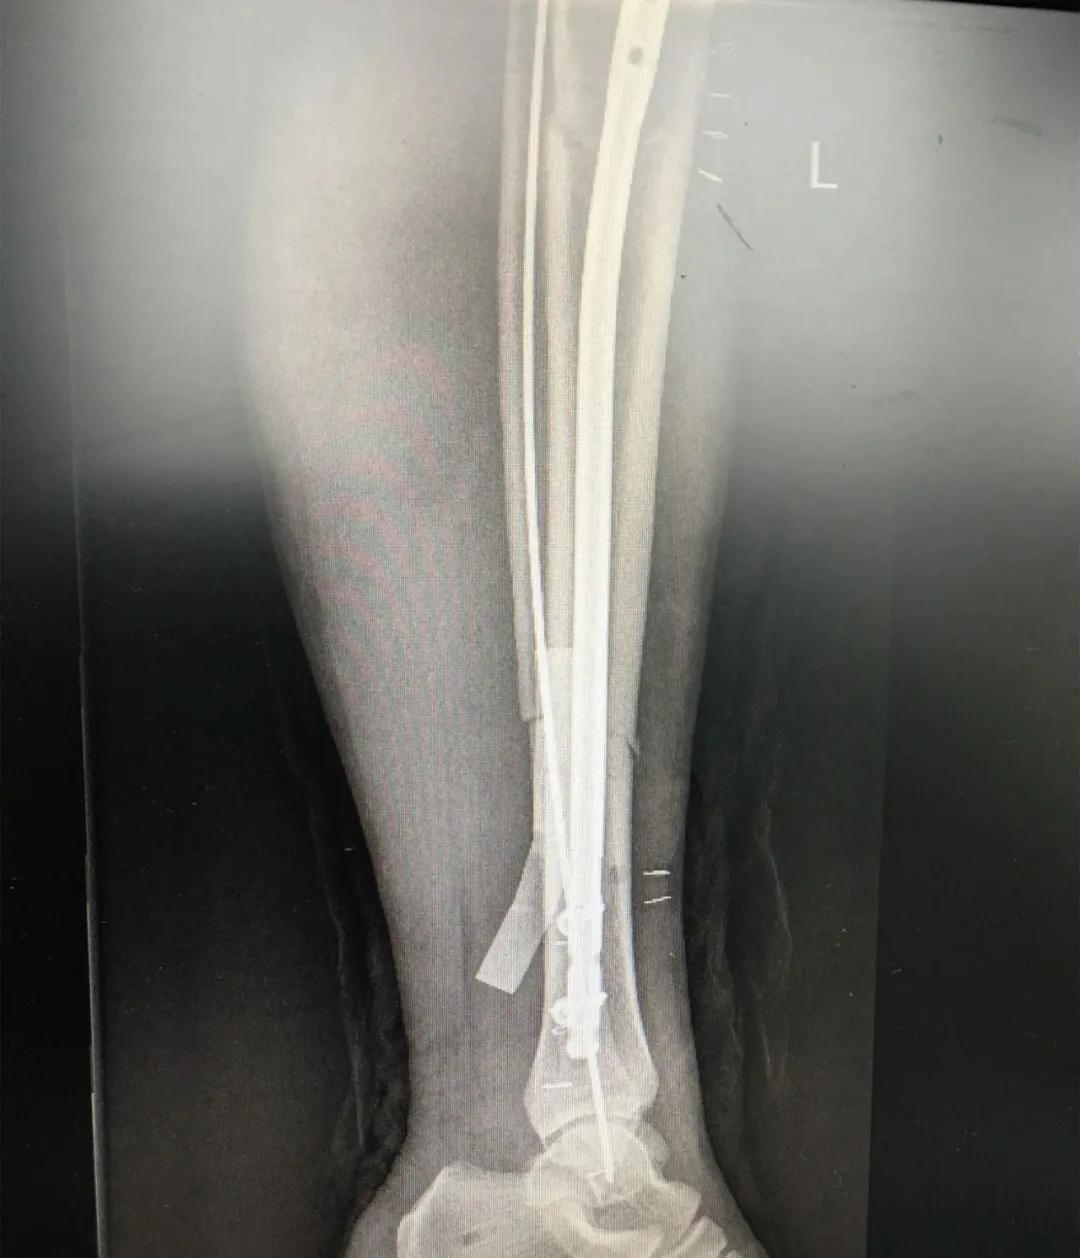

刘阿姨半个月前骑电动车时与小轿车相撞,导致了左胫腓骨粉碎性骨折,小腿骨碎成了三段。"然而,在术前丈夫周先生对刘阿姨的治疗却拿不定主意。“我妻子身上有多种基础疾病,患高血压15年,糖尿病也有8年多了。这里的诊疗技术,能不能保障手术的安全?手术前,我们家属的心中确实也很忐忑!"由于对我院创伤技术水平不太了解,周先生已经准备要转院治疗。

为患者实施的骨折微创复位固定技术是创伤骨科的特色技术。相较传统手术需要20公分的切口,微创手术只需要3公分左右。闭合复位髓内钉固定技术、经皮插板内固定技术(mippo技术)、闭合复位空心螺钉固定技术等一系列的微创复位固定技术,具有切口小、出血少、创伤小、愈合快、疤痕小等优点,骨折术后并发症明显降低,患者还可以早期负重功能锻炼。

另一位患者朱先生因车祸导致了右胫腓骨骨折,同样的小腿三段骨折,实施了微创闭合复位髓内钉固定术后,目前已经逐步进行康复功能锻炼。